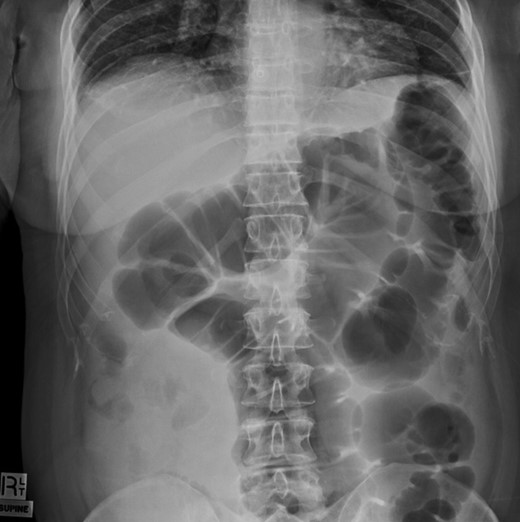

Colonoscopy revealed melanosis coli, diverticulosis and grade four hemorrhoids. She was admitted overnight following haemorrhoidectomy. The following morning she complained of abdominal pain, which she described similar to diverticulitis, and she was tender on exam. To rule out perforation, a plain film abdomen was performed. Findings were suggestive of gaseous distension following colonoscopic air insufflation without evidence of free gas (Fig. 1). Watchful waiting approach was adopted, however the patient deteriorated further during the course of the day. She had a vasovagal episode with tachycardia (134 bpm) and hypotension (67/47 mmHg). A venous blood gas revealed lactate level of 7 mmol/l. She underwent an urgent CT with findings suggestive of pericaecal internal hernia with the ileal loops located in the right paracolic gutter demonstrating features of ischemia (Fig. 2). There was moderate amount of free fluid, but no free gas to suggest perforation (Fig. 3). She was taken to theater that day for emergency laparotomy. The intraoperative findings included two litres of bloodstained fluid and floppy cecum with a band of adhesion to its own mesenteric base, probably adhesional having developed after the appendicectomy. This band has created a window through which three quarters of her small bowel had herniated and became strangulated. The bowel looked very ischemic, but not necrosed. The surgeons divided the adhesion, untwisted the small bowel and waited 20 minutes to allow sufficient time for bowel ischemia to recover. Fortunately, she did not require any bowel resection.

CT coronal view showing pericaecal internal hernia of ileal loops demonstrating features of ischemia.